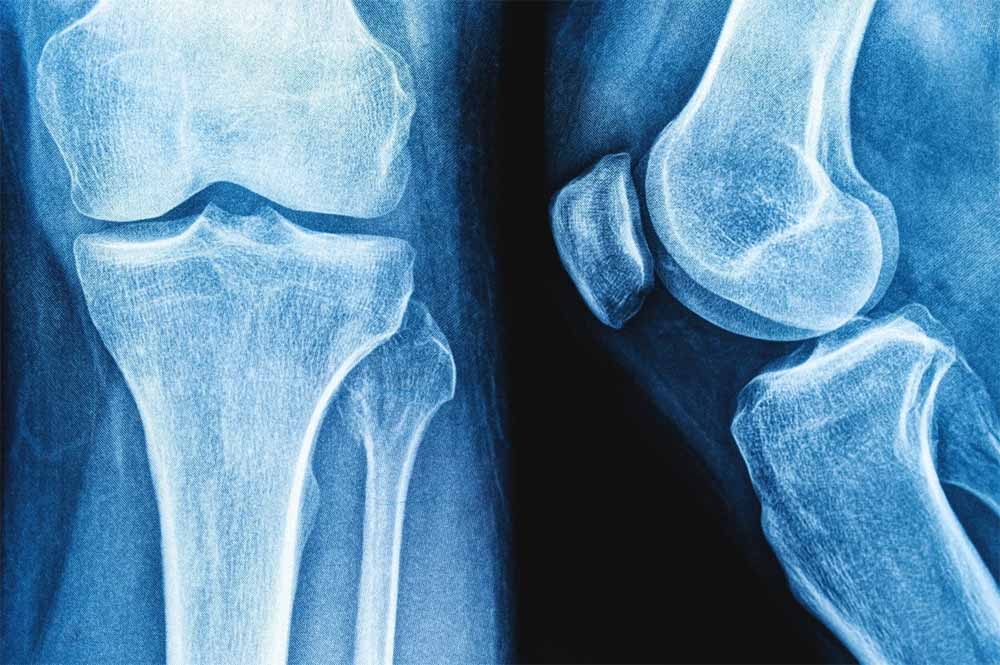

राष्ट्रीय प्रौद्योगिकी संस्थान (एनआईटी) राउरकेला के शोधकर्ताओं ने मानव शरीर में पाई जाने वाली प्राकृतिक शर्करा जैसे अणु हड्डियों के निर्माण और मरम्मत के लिए जिम्मेदार प्रोटीन, बोन मॉर्फोजेनेटिक प्रोटीन-2 के व्यवहार को कैसे प्रभावित कर सकती है? इसका पता लगाया है।

प्रतिष्ठित पत्रिका बायोकैमिस्ट्री में प्रकाशित इस शोध के निष्कर्षों का उपयोग हड्डी और उपास्थि पुनर्जनन के उन्नत उपचार, बेहतर इम्प्लांट और अधिक प्रभावी प्रोटीन-आधारित दवाओं के विकास में किया जा सकता है। प्रोटीन मनुष्य के शरीर में विभिन्न कार्य करते हैं। टिश्यू के निर्माण और रासायनिक प्रतिक्रियाओं में सहयोग देने से लेकर कोशिकाओं के बीच संकेतों के रूप में कार्य करने तक बड़ी जिम्मेदारी निभाते हैं।

हालांकि सर्वोत्तम उत्पादकता के लिए इनका त्रि-आयामी आकृतियों में सटीक मुड़ना या खुलना आवश्यक है। प्रोटीन क्यों और कैसे खुलते हैं? यह समझना जीव विज्ञान का एक प्रमुख लक्ष्य है। इसका प्रभाव चिकित्सा, जैव प्रौद्योगिकी और ड्रग डिलिवरी पर पड़ता है। इस संदर्भ में हड्डी और उपास्थि के निर्माण, चोटों को ठीक करने और स्टेम कोशिकाओं को अस्थि-निर्माण कोशिकाओं में परिणत करने में बीएमपी-2 महत्वपूर्ण भूमिका निभाता है।